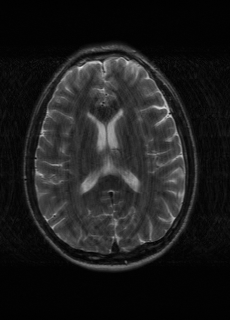

As we observe from the right image in Fig. 2, our BRM, both from MIMO and SISO settings, predicts the performance of dedicated models with a high correlation. We further choose the best three , and perform the last stage of fine-tuning accordingly to (6). A visual evaluation on real data is shown in Fig. 3. For simulated data, please refer to the Supplemental Material section.

Base on the best performing , we perceive that among , , and FLAIR, the results are best when is sampled the most. We suggest that this makes intuitive sense as images provide the best contrast out of the three sequences, which can compensate for the details lost in other images. The same observation can be made on the simulated data, where both and FLAIR show good contrast. When the time setting is changed to non-uniformity, we can see that our search for the best sampling strategy reflects the change. is sampled more as a result of faster acquisition time, while is still sufficiently sampled.

| Sequence | LR | SISO | MIMO | MIMO tuned | GT |

|---|---|---|---|---|---|

(a) 34.38/0.9371

(a) 34.38/0.9371

|

(b) 42.42/0.9883

(b) 42.42/0.9883

|

(c) 44.60/0.9920

(c) 44.60/0.9920

|

(d) 45.50/0.9940

(d) 45.50/0.9940

|

(e) PSNR/SSIM

(e) PSNR/SSIM

|

|

(f) 29.74/0.8903

(f) 29.74/0.8903

|

(g) 36.25/0.9734

(g) 36.25/0.9734

|

(h) 36.42/0.9752

(h) 36.42/0.9752

|

(i) 37.70/0.9832

(i) 37.70/0.9832

|

(j) PSNR/SSIM

(j) PSNR/SSIM

|

|

(k) 39.89/0.9311

(k) 39.89/0.9311

|

(l) 43.94/0.9864

(l) 43.94/0.9864

|

(m) 44.74/0.9883

(m) 44.74/0.9883

|

(n) 45.49/0.9894

(n) 45.49/0.9894

|

(o) PSNR/SSIM

(o) PSNR/SSIM

|